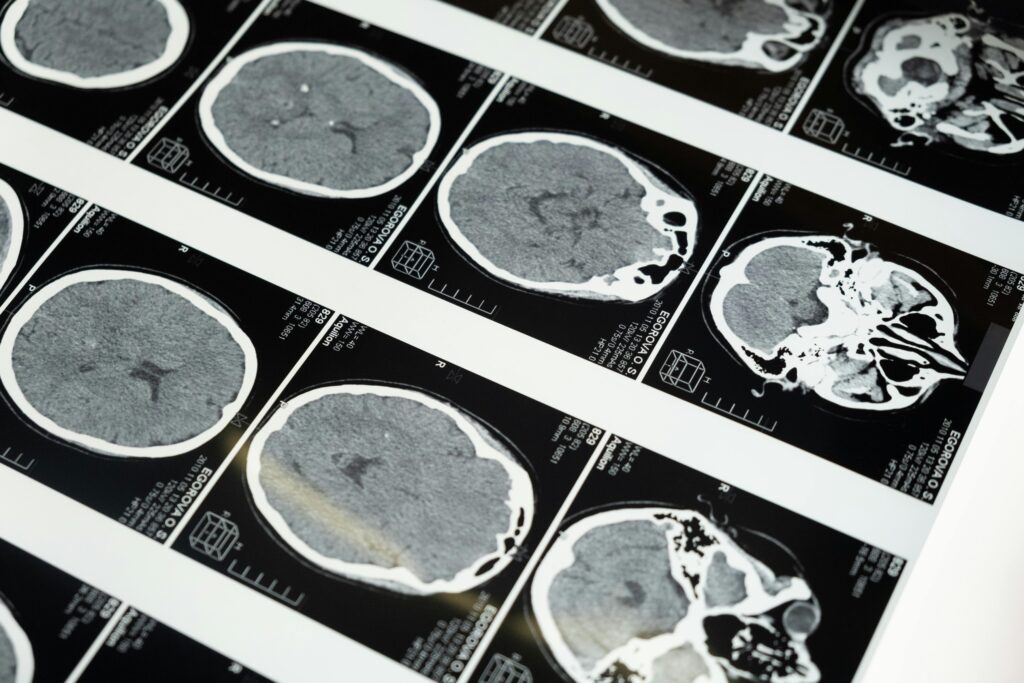

Mediante técnicas avanzadas, los investigadores analizaron más de 30 metales en cerebros humanos. Solo el litio mostró diferencias notables entre personas sanas y aquellas con deterioro cognitivo o Alzheimer avanzado. Lo más sorprendente: incluso en las primeras etapas de pérdida de memoria, los niveles de litio ya eran más bajos. Esto sugiere que mantener su equilibrio podría ser clave para retrasar el avance de la enfermedad.